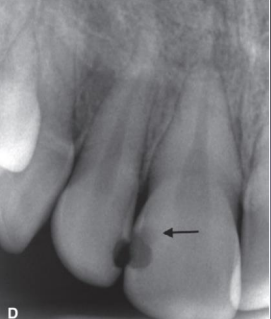

classify this lesion based on the ADA caries classification system

D3

how do buccal and lingual caries show up in a radiograph

well-defined ovoid radiolucency

buccal/lingual caries may often be confused w occlusal caries due to superimposition, how can you sort of differentiate them

occlusal usually not as well-defined (pic shows B/L caries)